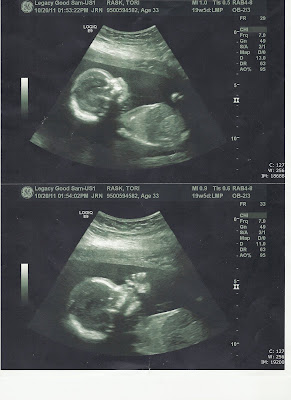

Converting the guest room to his room is the latest in the series of milestones that have felt like they would NEVER come. The first was the 6-week checkup on Jeff's birthday when we first saw his heartbeat, then it was announcing and telling people at 10-12 weeks, then it was the BIG ultrasound at 18 weeks, now it's setting up his room over Christmas break (29 weeks tomorrow), next we start birthing classes in a week and a half! Crazy! All of these milestones have come... maybe his actual birth will get here someday, too, although it seems so far away because we are so excited!